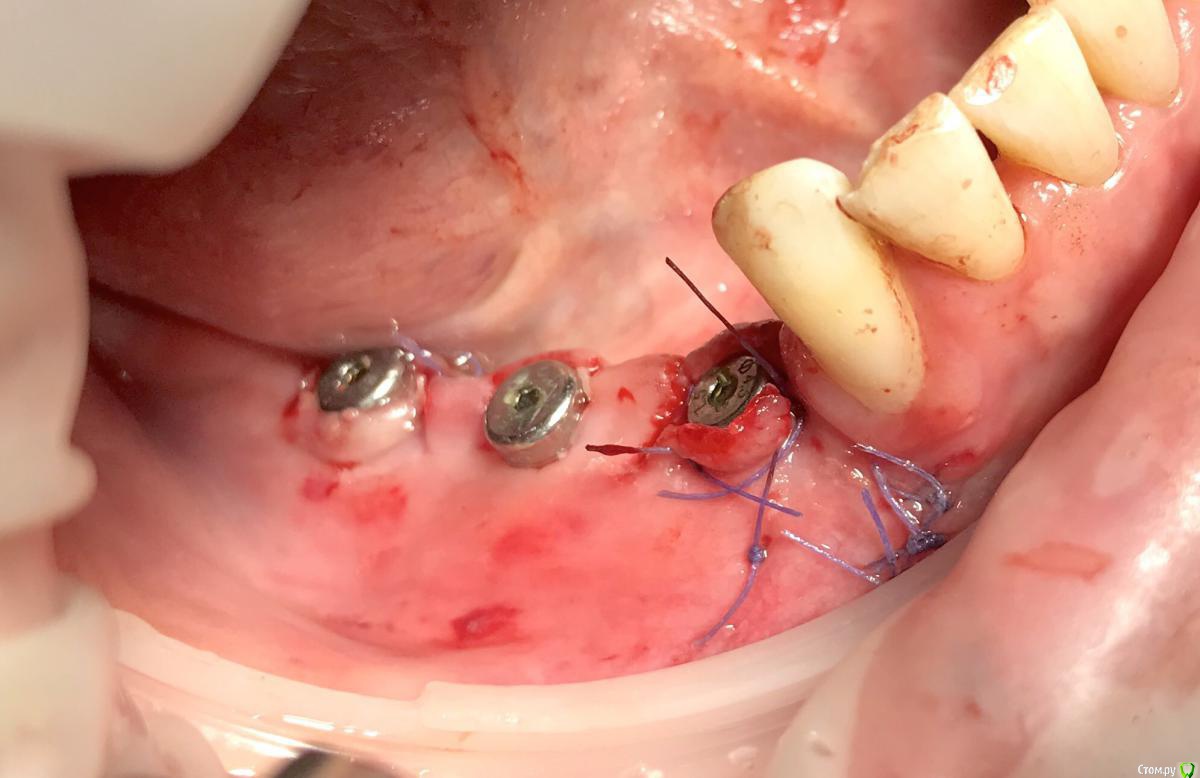

колесников Опубликовано 25 ноября, 2018 Поделиться Опубликовано 25 ноября, 2018 Фото для примера,из разряда было-стало. Обычно рядовые случаи не фотографирую,но тут решил запечатлеть. Тоннель плюс имплантация,делал впервые. Примерно понятно как узкий гребень превращается в широкую сосиску. 2 Ссылка на комментарий

колесников Опубликовано 25 ноября, 2018 Поделиться Опубликовано 25 ноября, 2018 Как герметичности добиваюсь? Просто. Разрез в стороне от зоны аугментации. Сложности бывают в тоннелировании, когда встречаются участки рубцовых спаек,при тупом отслаивании возможны разрывы и перфорации.Результат ожидаемый-плотный аугментат. Фото скелетированого гребня нет,я не откидываю лоскут . 1 Ссылка на комментарий

колесников Опубликовано 26 ноября, 2018 Поделиться Опубликовано 26 ноября, 2018 Ну как бы ,да. Просто графт под надкостницу. Есть конечно тонкости и ньюансы,но в целом все так. Производители мембран ,пинов и прочего дорогостоящего балласта идут лесом. По этому наверно курсов не будет по теме,не выгодно. Если кто был на курсе Р.Ядоха,он несколько раз обмолвился про новую перспективную тему:каркас для десны из ксенографта-это о тоннелировании. Ссылка на комментарий

колесников Опубликовано 26 ноября, 2018 Поделиться Опубликовано 26 ноября, 2018 Скажите плз, импланты одномоментно с графтингом, если да , то какой шаблон, по КТ?Да,тут одномоментно. Хорошо это или нет,будет ли все удачно-не могу сказать,делал так впервые,главное понять как это работает.Делать отсроченно мне уже скучно. Повторять не рекомендую. Шаблон не использовал,он тут не поможет,гребень 2мм. Ссылка на комментарий